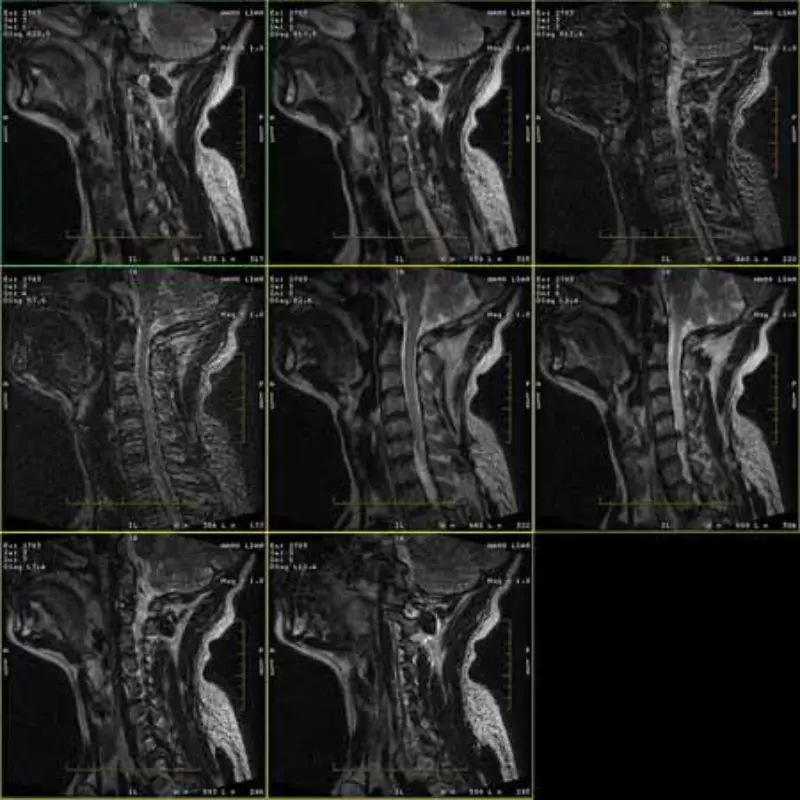

Obrázky protokolů FRFSE a GRE mají duchy a někdy se v jedné sérii objevují obrázky s nízkým SNR. Ale snímky protokolu SE jsou normální.

Podívejte se prosím na obrázky v příloze.